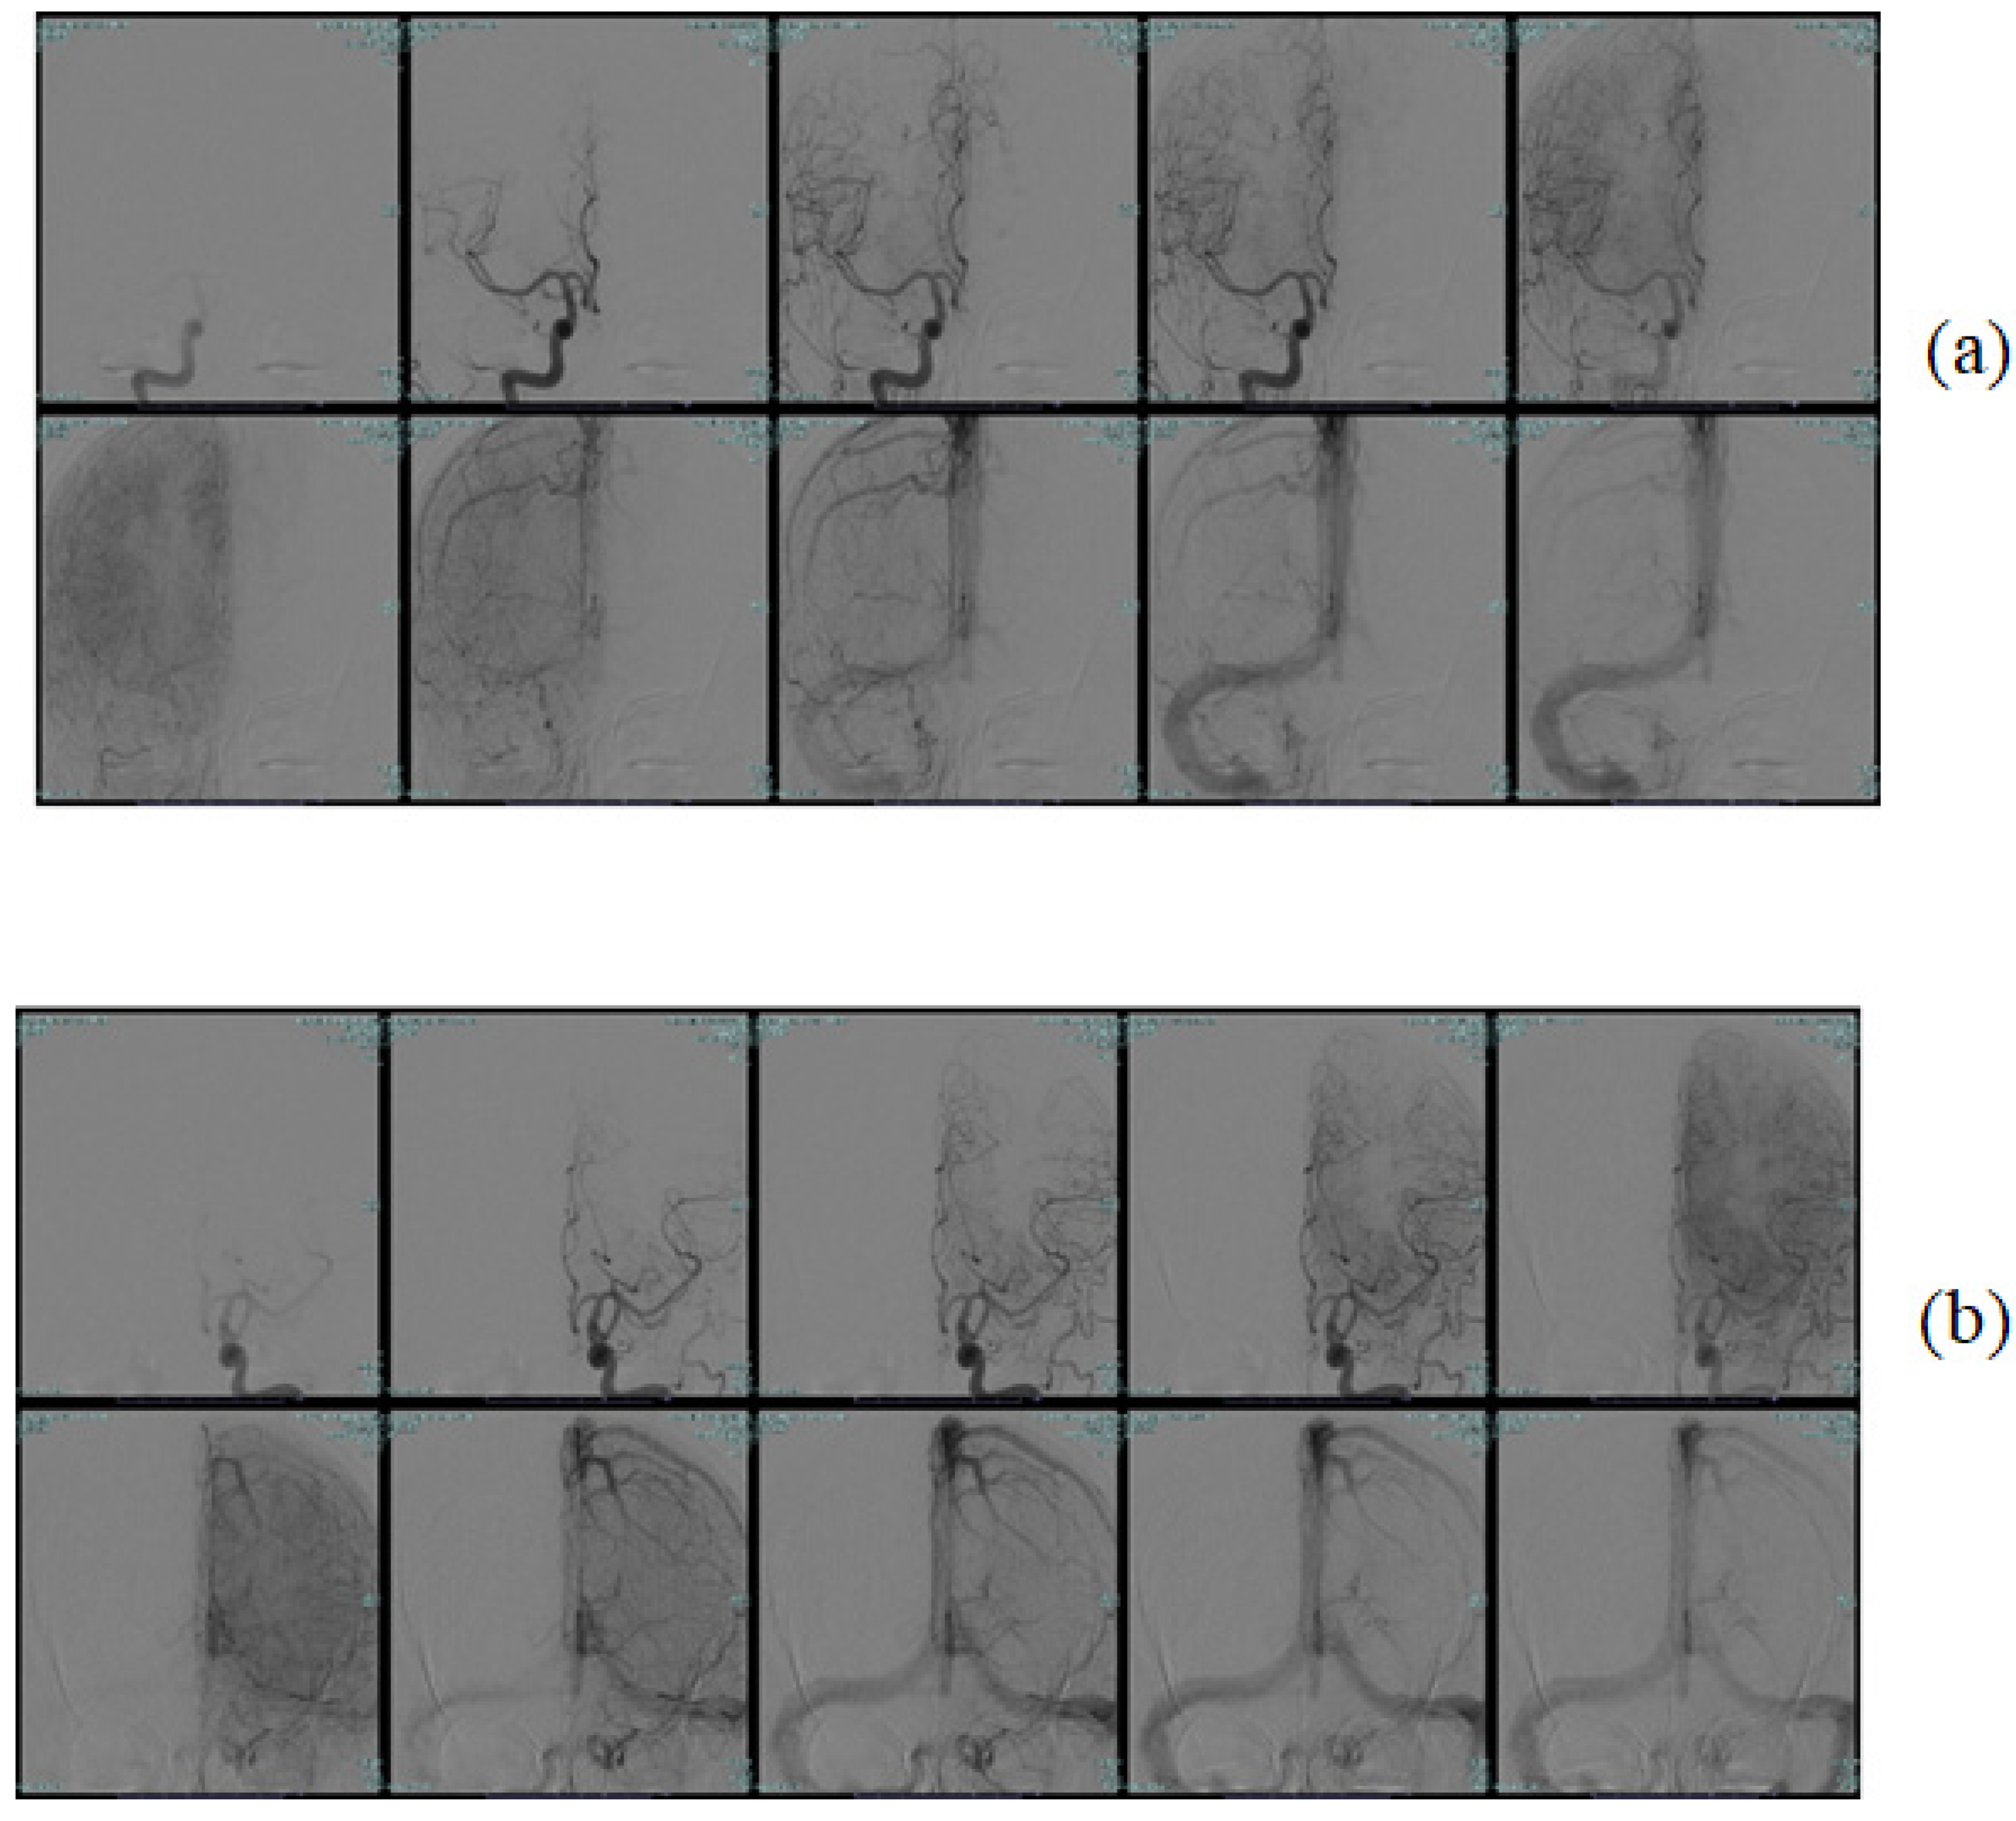

3.1. Dataset Used

3.2. Preprocessing and Augmentation